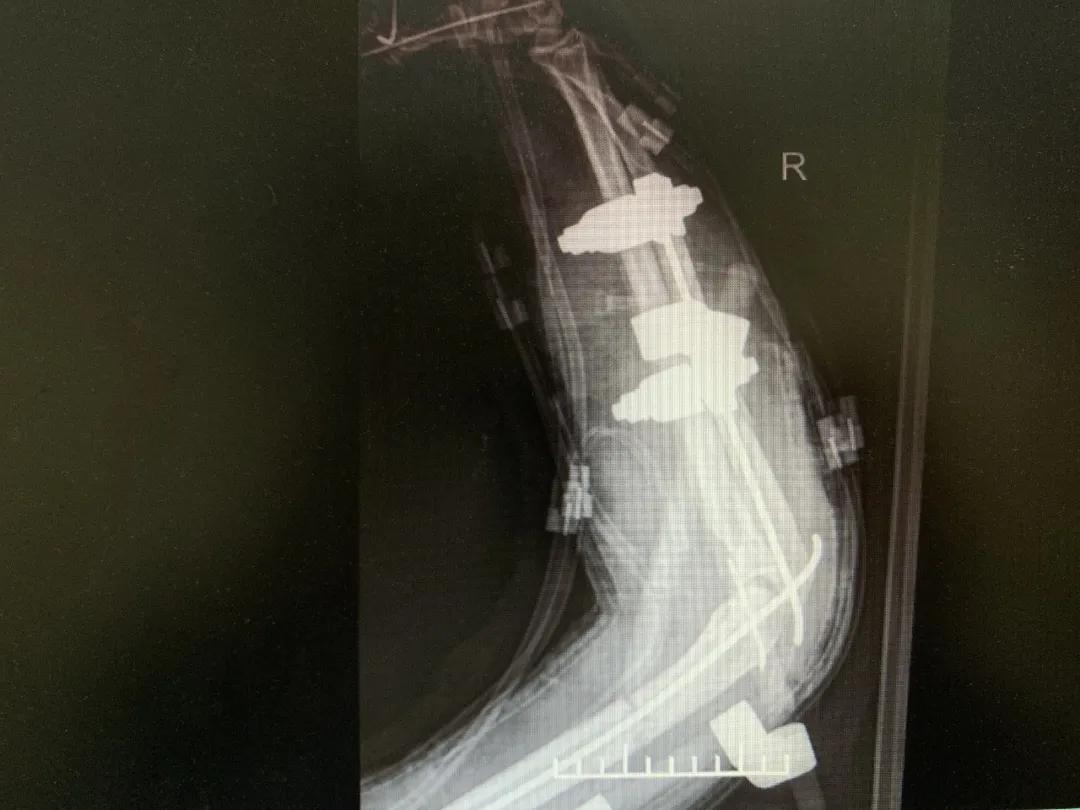

“正常的肢体都有皮肤保护着,如果没有皮肤,我们的肌肉、血管、神经、骨骼露在外面,都会发生坏死。”苑芳昌介绍,伤者的情况非常复杂,伴有多发骨折、肱骨骨折、骨关节的多发错位,还有腕部的骨折,更有血管、神经损伤。不仅如此,伤者右臂在机器里面受到绞伤,肌肉也已经大面积挫伤,各种复杂情形交织在一起甚至让手术“无从下手”。

“缺失皮肤用VSD辅料覆盖,保护着创面……”骨科二病区主治医师杨金虎介绍,手术过程非常考验医生的清创彻底性以及对上肢解剖的熟练程度,还有对人体血管、神经的显微外科运用技术,“这就要求医生对皮肤、肌肉的活性有准确判断,如果坏死的肌肉保留太多,坏死的组织会影响病人全身情况。”

清创、止血、接骨、将粉碎的骨块一块块拼接完整,同时给予VSD敷料负压引流。经过三次清创清除后,明确了坏死的皮肤等组织,创面好转,肉芽组织良好……

“前臂及手指血运缓缓流淌,肢体恢复血供,血运重建获得成功!”次日凌晨4时20分,患者被推出手术室。但是,几次清创后患者前臂皮肤出现大面积缺失,如不及时进行植皮覆盖修复手术,病人极有可能会继发感染,“极有可能造成前臂坏死肢体不保,那么前期所有的治疗和付出也就前功尽弃了。”